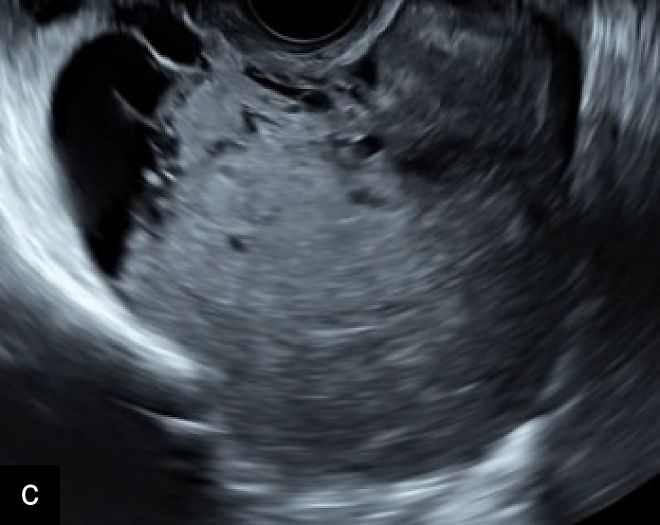

2

Transvaginal ultrasound images with color Doppler of uterine sarcoma, demonstrating heterogeneous echotexture and irregular margins. The Doppler assessment reveals variable vascularization patterns, ranging from moderate (a–b) to extensive (c) intralesional blood flow. Images (b) and (c) show the 'cooked appearance' of solid tissue, a sonographic feature defined by the lack of structure of the solid component and the absence of acoustic shadowing.